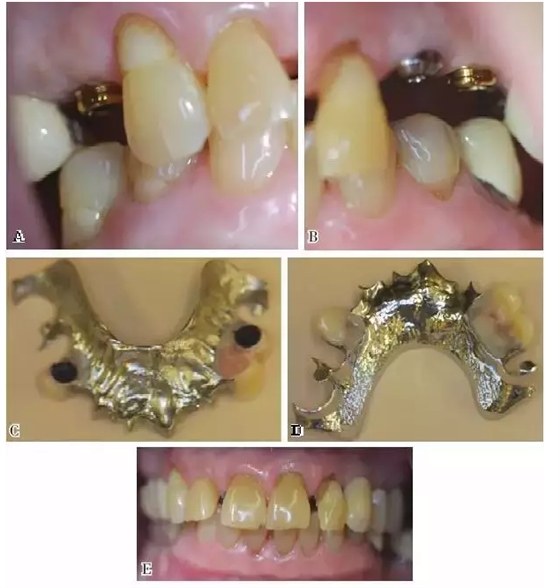

圖5:KennedyⅢ類缺損。3號牙位的種植體和天然牙的舌隆突及近中牙合支托提供了支持力,5號和12號牙位的種植體提供固位力。導(dǎo)平面增強了種植體的固位力,因而不再需要卡環(huán)

圖6:采用種植體的KennedyⅢ類可摘局部義齒,患者為老年患者,頜間距離較小,又不愿使用卡環(huán)。義齒人工牙按照美觀原則修整和排列,使用丙烯酸樹脂塑造牙合面形態(tài)并連接于支架和附著體外罩上